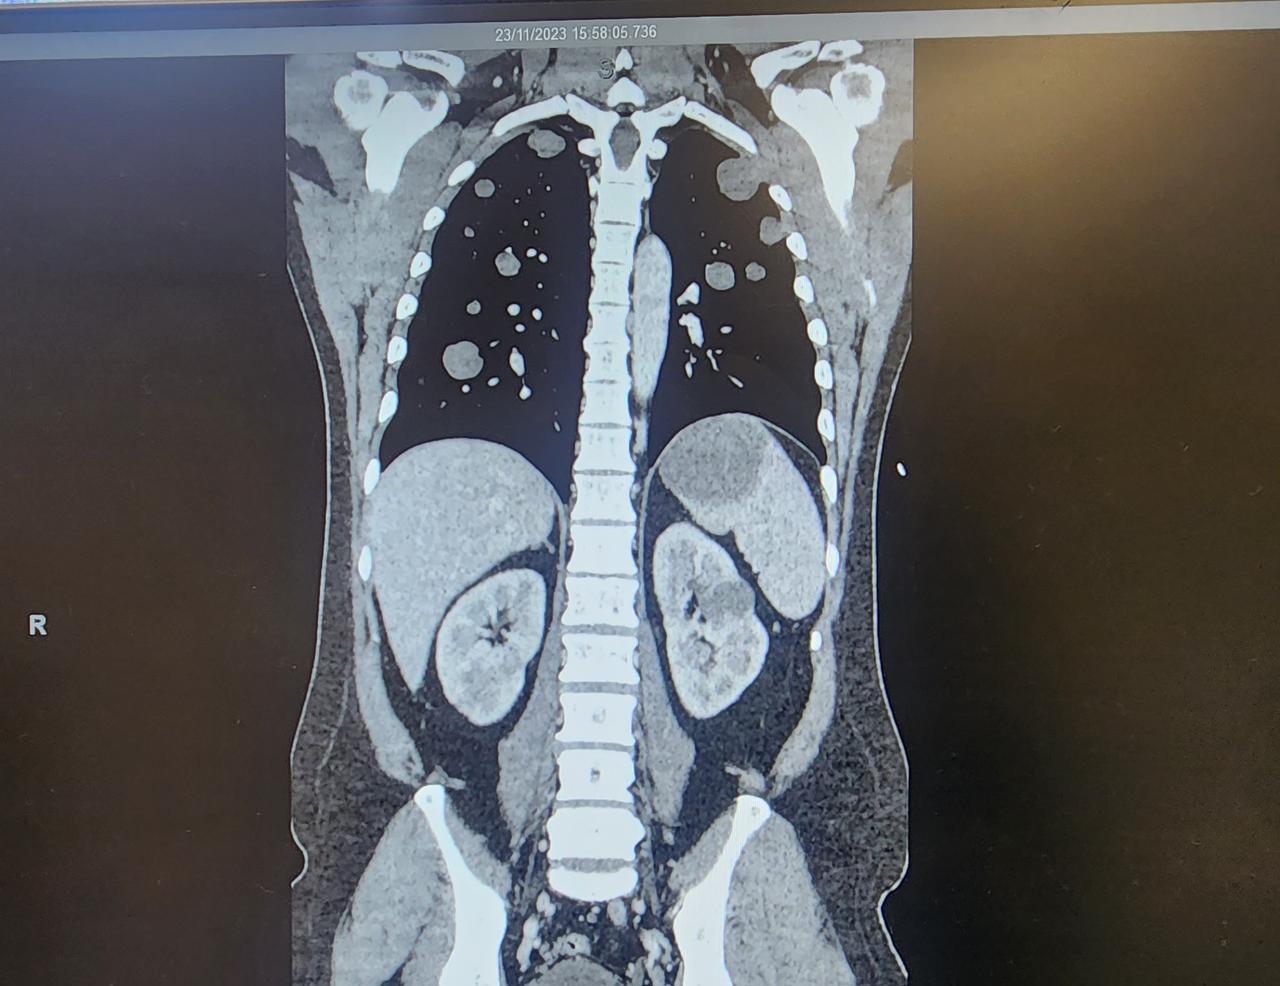

This chemo treatment will be his last. Sadly we have found that it was shrinking BUT also spreading to other parts of his body. Because he has Metastatic Choriocarcinoma, the chemo just bought us a bit of time. So from next year onwards, he will have regular blood tests and CT scans to HOPEFULLY stay on top of it. Because his cancer is a rare form; theres not much they know about it. Apparently only 1% out of 10,000 males get it! 😥

Sooooo.. update. MyLove is starting his chemo tumoro. Then from Monday 2nd October he will be having 5 days of treatment. The following week will be 1 day and the following after that will be 1 day. They will carry this on for 4 cycles and HOPEFULLY it would have shrunk to very minimal or all gone.

However, there is another part on the top of the brain that they hadn't removed as the one removed was already high risk and a bit bigger then they thought. They told me the flash name for the cancer which I have already forgotten BUT, we now know what it is and where it has come from.

But thats where its at atm and they said chemo is going to be the best chance for us to get rid of all or most of the cancer floating around his body. Fingers and toes crossd! 🤞🤞